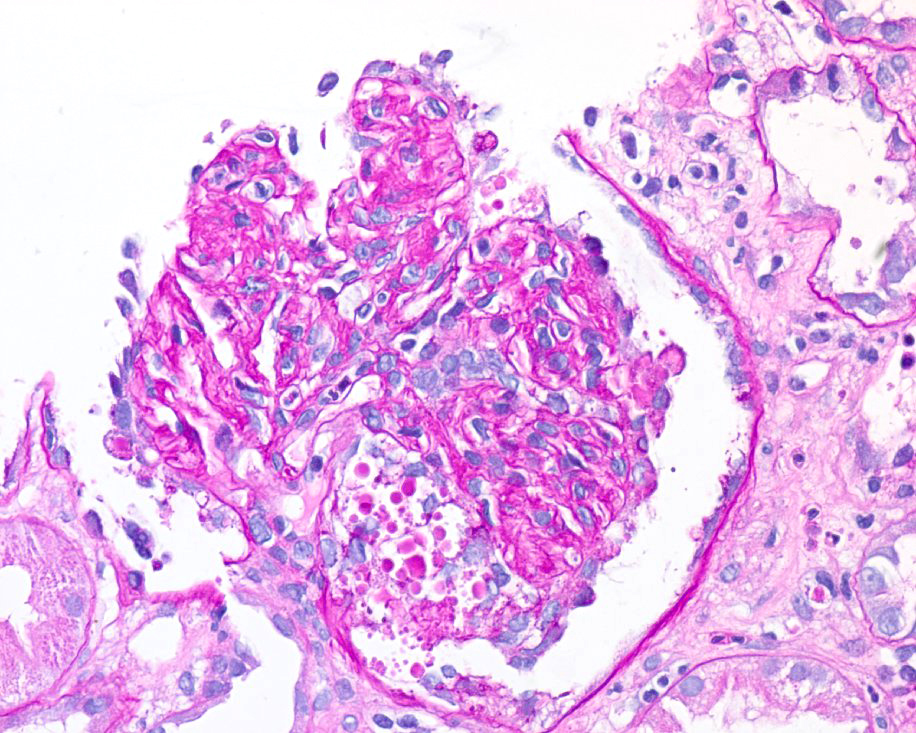

How about our patient with COVID-19 and nephrotic syndrome? The biopsy reveals collapsing FSGS!

Above, we see collapse of the capillary loops along with hypertrophy and hyperplasia of the podocytes. We also see effaced podocytes under electron microscopy (EM). Viruses have been commonly associated with collapsing FSGS or collapsing glomerulopathy (think: human immunodeficiency virus (HIV), cytomegalovirus (CMV), parvovirus B19) – and seem SARS-CoV2 has been added to the list: meet COVAN (COVID-19 associated nephropathy). Collapsing glomerulopathy has been reported in individuals of African ancestry with COVID-19 and high-risk apolipoprotein 1 (APOL1) alleles. A proposed pathogenesis of COVAN is summarized in the figure below.